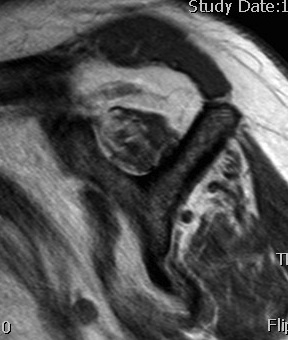

Full thickness rotator cuff tears

Partial bursal sided tear Partial articular sided tears

Subscapularis tears

Small full thickness rotator cuff tear of supraspinatus - retracted to footprint

Large full thickness tear of supraspinatus and infraspinatus tendon - retracted to midhumeral head

Massive rotator cuff tear of the supraspinatus and infraspinatus tendon - retracted to glenoid